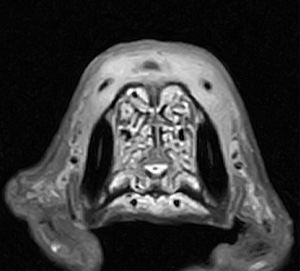

5~6歳以上の去勢手術をしていないオス犬に多い病気ですが、メス犬や去勢した犬に起こることもあります。お尻の筋肉が萎縮した結果、筋肉の隙間から直腸や膀胱が皮膚の下にとびでてしまいます。これにより便が出にくくなったり膀胱炎になったりします。手術をすることで機能回復および今後の致死的な状況を回避することができます。当院では去勢手術→結腸固定→前立腺固定→骨盤隔膜構成筋の縫縮→内閉鎖筋フラップ→浅臀筋フラップの順で通常腹側・臀部左右両側同時に行います。また老化以外に、筋肉が萎縮する原因があったり、腹圧がかかる原因があったりする場合も多いので、再発防止のためそれらの診断・治療も重要です。今回のワンちゃんも無事手術も終わり元気に退院しました。よかったね。